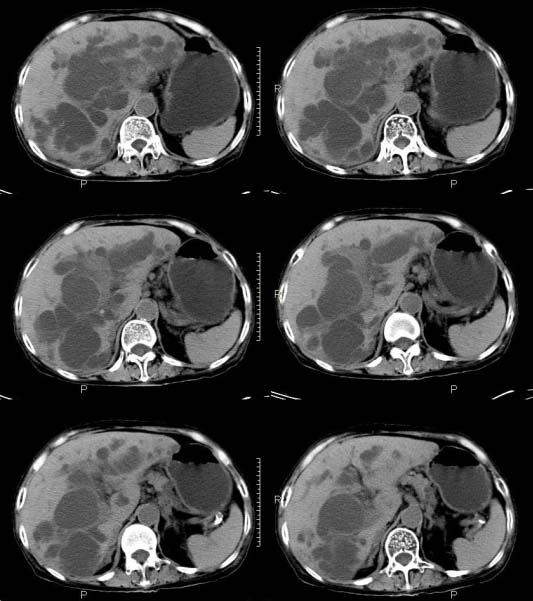

女,71岁,腹痛、腹胀、黄疸20余天,b超示肝内外胆管高度扩张内伴絮状物质(未提示梗阻部位或结石影),经抗炎解痉治疗后,肝功能有所好转,但胆道梗阻状态并未减轻。患者曾于1970年代做过胆囊切除术,1997年因胰腺炎而手术;且患者有糖尿病10余年。ct图片传了静脉期,未传动脉期了,最后一序列为3.2mm薄扫,请各位同仁仔细看看,确定一下胆管梗阻的部位,是炎性梗阻还是肿瘤性梗阻,是否与胰腺炎有关系,扩张胆总管中段前缘是否是胰管。请高手们最好用图示来指出梗阻部位。

请大家看看扩张的胆总管内见一弧线形间隔,怎样解释?

肝内外胆管显著扩张,考虑先天性胆管囊肿(ⅳ型)。

肝内胆管远侧、近侧不比例扩张,以近侧为明显。胆总管扩张。考虑先天性胆管囊肿(ⅳ型)。